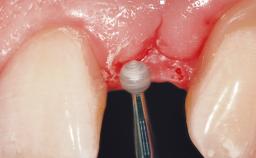

Placement Protocol Immediate implant placement

Socket Morphology Single-root socket

Socket Integrity Sufficient, with intact bone walls